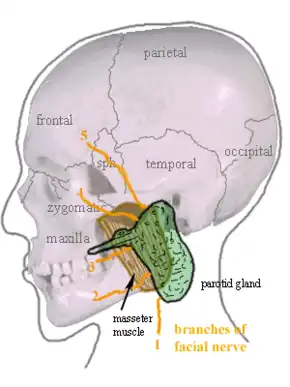

Location of the left parotid gland in humans (shown in green). | |

The parotid gland is a major salivary gland in many animals. In humans, the two parotid glands are present on either side of the mouth and in front of both ears. They are the largest of the salivary glands. Each parotid is wrapped around the mandibular ramus, and secretes serous saliva through the parotid duct into the mouth, to facilitate mastication and swallowing and to begin the digestion of starches. There are also two other types of salivary glands; they are submandibular and sublingual glands.[1] Sometimes accessory parotid glands are found close to the main parotid glands.[2]

The parotid glands are a pair of mainly serous salivary glands located below and in front of each ear canal, draining their secretions into the vestibule of the mouth through the parotid duct.[4] Each gland lies behind the mandibular ramus and in front of the mastoid process of the temporal bone. The gland can be felt on either side, by feeling in front of each ear, along the cheek, and below the angle of the mandible.[5]

A number of different structures pass through the gland. From lateral to medial, these are:

- Facial nerve

- Retromandibular vein

- External carotid artery

- Superficial temporal artery

- Branches of the great auricular nerve

- Maxillary artery

The facial nerve (CN VII) splits into its branches within the parotid gland, thus forming its parotid plexus. Nerves of this plexus then pass through the parotid gland without innervating the gland itself.[6]